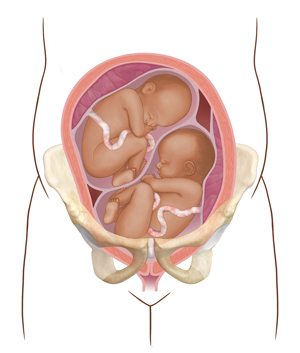

More than 1 baby. With two or more babies, one is more likely to be in the wrong position.

|

| More than one baby |